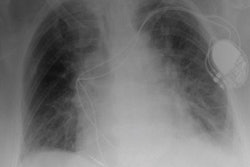

Understanding the challenges with implementing artificial intelligence (AI) in radiology can help organizations and research groups decide the best approach for their AI endeavor and set strategic priorities, but what are the issues that need careful thought and planning in what could be a minefield of technical and organizational missteps? Panagiotis Korfiatis, PhD, AI scientist in the radiology department of the Mayo clinic tackled these questions on November 28 at RSNA in Chicago.

Whether departments are seeking to deploy commercialized or in-house produced AI algorithms stakeholders need to address a raft of fundamental considerations before integrating AI tools into the clinical workflow.